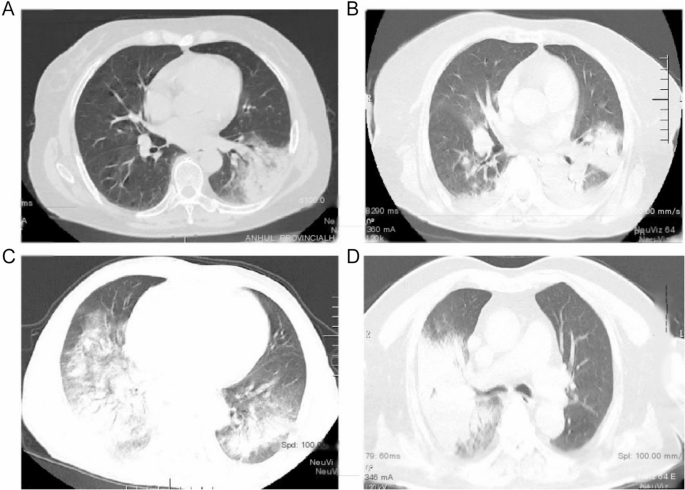

Credit: bmcinfectdis.biomedcentral.com